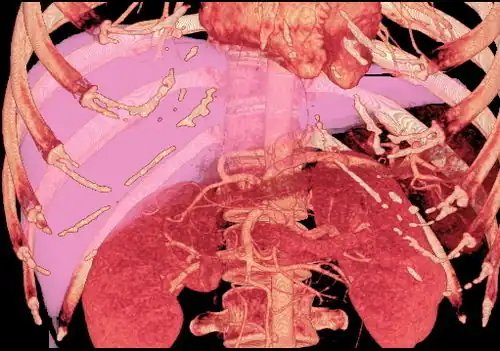

Couinaud classification system

Shape of human liver in animation, with eight Couinaud segments labelled

In the widely used Couinaud system, the functional lobes are further divided into a total of eight subsegments based on a transverse plane through the bifurcation of the main portal vein.[30] The caudate lobe is a separate structure that receives blood flow from both the right- and left-sided vascular branches.[31][32] The Couinaud classification divides the liver into eight functionally independent liver segments. Each segment has its own vascular inflow, outflow and biliary drainage. In the centre of each segment are branches of the portal vein, hepatic artery, and bile duct. In the periphery of each segment is vascular outflow through the hepatic veins.[33] The classification system uses the vascular supply in the liver to separate the functional units (numbered I to VIII) with unit 1, the caudate lobe, receiving its supply from both the right and the left branches of the portal vein. It contains one or more hepatic veins which drain directly into the inferior vena cava.[30] The remainder of the units (II to VIII) are numbered in a clockwise fashion:[33]

With the recent advances of noninvasive imaging, living liver donors usually have to undergo imaging examinations for liver anatomy to decide if the anatomy is feasible for donation. The evaluation is usually performed by multidetector row computed tomography (MDCT) and magnetic resonance imaging (MRI). MDCT is good in vascular anatomy and volumetry. MRI is used for biliary tree anatomy. Donors with very unusual vascular anatomy, which makes them unsuitable for donation, could be screened out to avoid unnecessary operations.